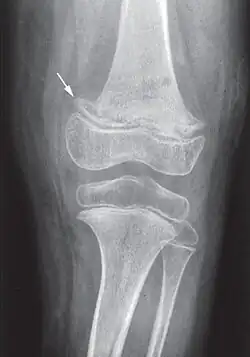

X-ray of the knee joint (arrow indicates scurvy line)

Vitamins are essential to the production and use of enzymes in ongoing processes throughout the human body.[8] Ascorbic acid is needed for a variety of biosynthetic pathways, by accelerating hydroxylation and amidation reactions.